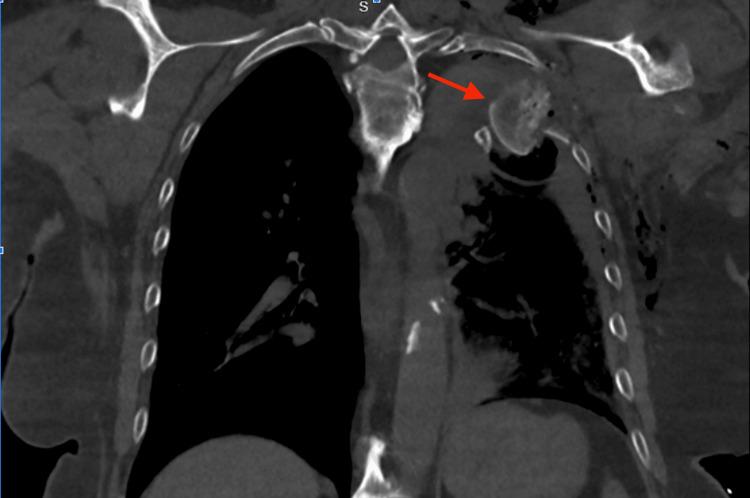

胸腔内肱骨头骨折:一例报告

An intrathoracic humeral head fracture is a rare injury usually caused by a high-energy force to the shoulder, resulting in medial displacement of the humeral head. This injury can be severe and life-threatening due to the proximity of the dislocated and fractured bone to the critical structures within the intrathoracic cavity. There are no current official guidelines for the treatment of such injuries. We report the successful treatment of a patient with an intrathoracic humeral head fracture that lacerated the thoracic aorta.

胸腔内肱骨头骨折是一种罕见的损伤,通常由肩部的高能暴力所致,导致肱骨头向内侧移位。由于脱位和骨折的骨头靠近胸腔内的关键结构,这种损伤可能很严重甚至危及生命。目前尚无针对此类损伤治疗的官方指南。我们报告了一例成功治疗的胸腔内肱骨头骨折患者,该患者的骨折撕裂了胸主动脉。